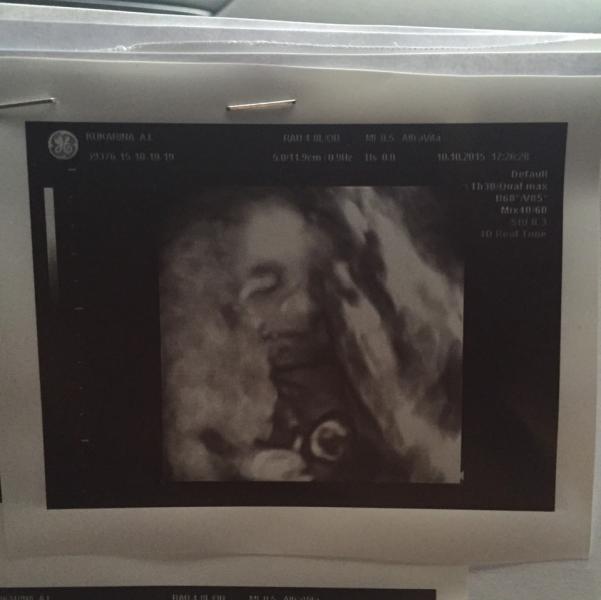

Вчера была опять у узиста Донова, очень мне он нравится, все к нас хорошо только фоткаться не любим!

Мы тоже у него были 6 дней назад, очень хороший узист! Тоже фоточек девчуля нашей наделал, рассказал все ее особенности от зубов до подъема ноги😀 На следующее узи тоже к нему поедем)